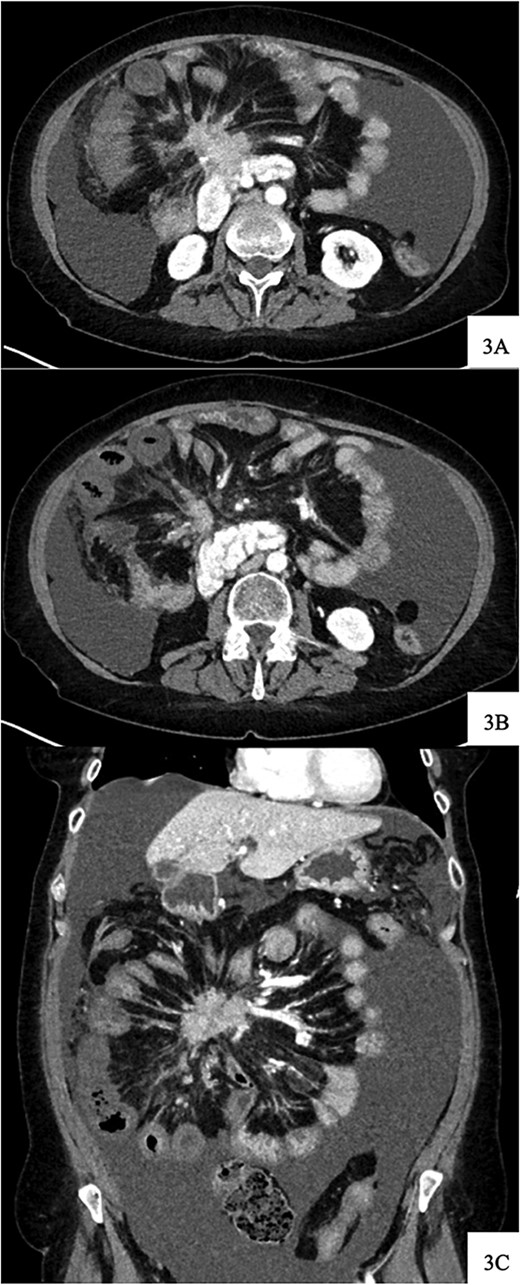

Contrast-enhanced axial CT image at time of presentation shows spiculated central mesenteric mass severe narrowing of the SMV with probably occlusion and encasement of the SMA with possible occlusion (A) associated with decreased enhancement and bowel wall thickening of several small bowel loops within the right lower quadrant (B). Coronal reformatting demonstrates the relationship of the mesenteric mass and affected small bowel (C).